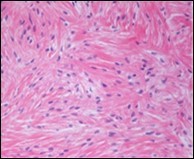

The neoplasm frequently infiltrates abutting skeletal muscle. Occasionally, tumefaction denominates hyper-cellular foci, tumour necrosis, cellular or nuclear atypia and mitotic figures, features which are characteristic of intermediate to high grade sarcoma. Localized tumour reoccurrence may be hyper-cellular with enhanced mitotic activity 4, 5. On ultrastructural examination, fibroblastic differentiation is exemplified 5. Figure 1, Figure 2, Figure 3, Figure 4, Figure 5, Figure 6, Figure 7, Figure 8.

Figure 3.Low grade fibromyxoid sarcoma demonstrating alternating fibrous and myxoid areas comprised of uniform spindle-shaped cells (11).